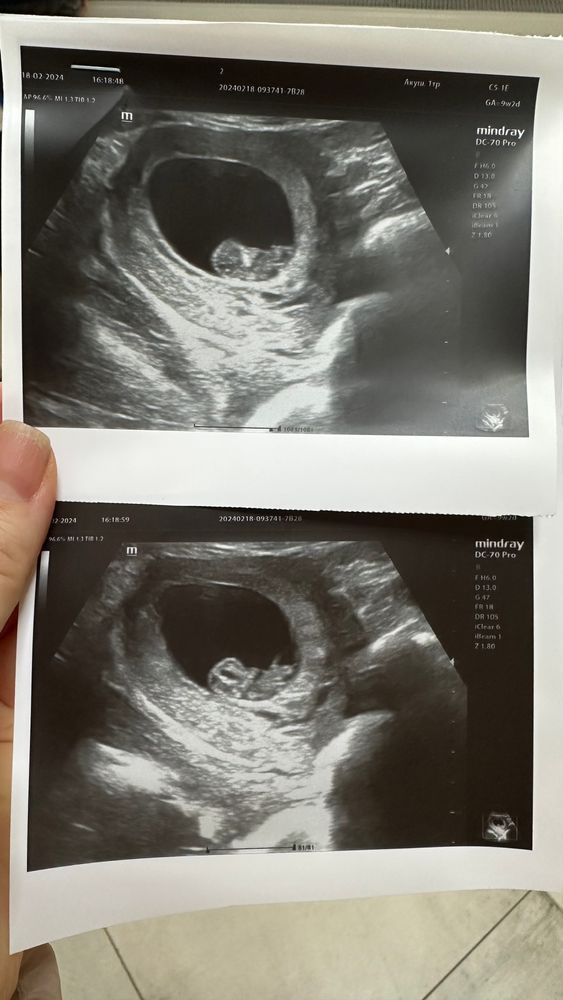

УЗИ 9 недель 2 дня

Когда вы пошли на первое узи? Моя первая беременность, ещё не знаю, чтобы уже послушать сердечко